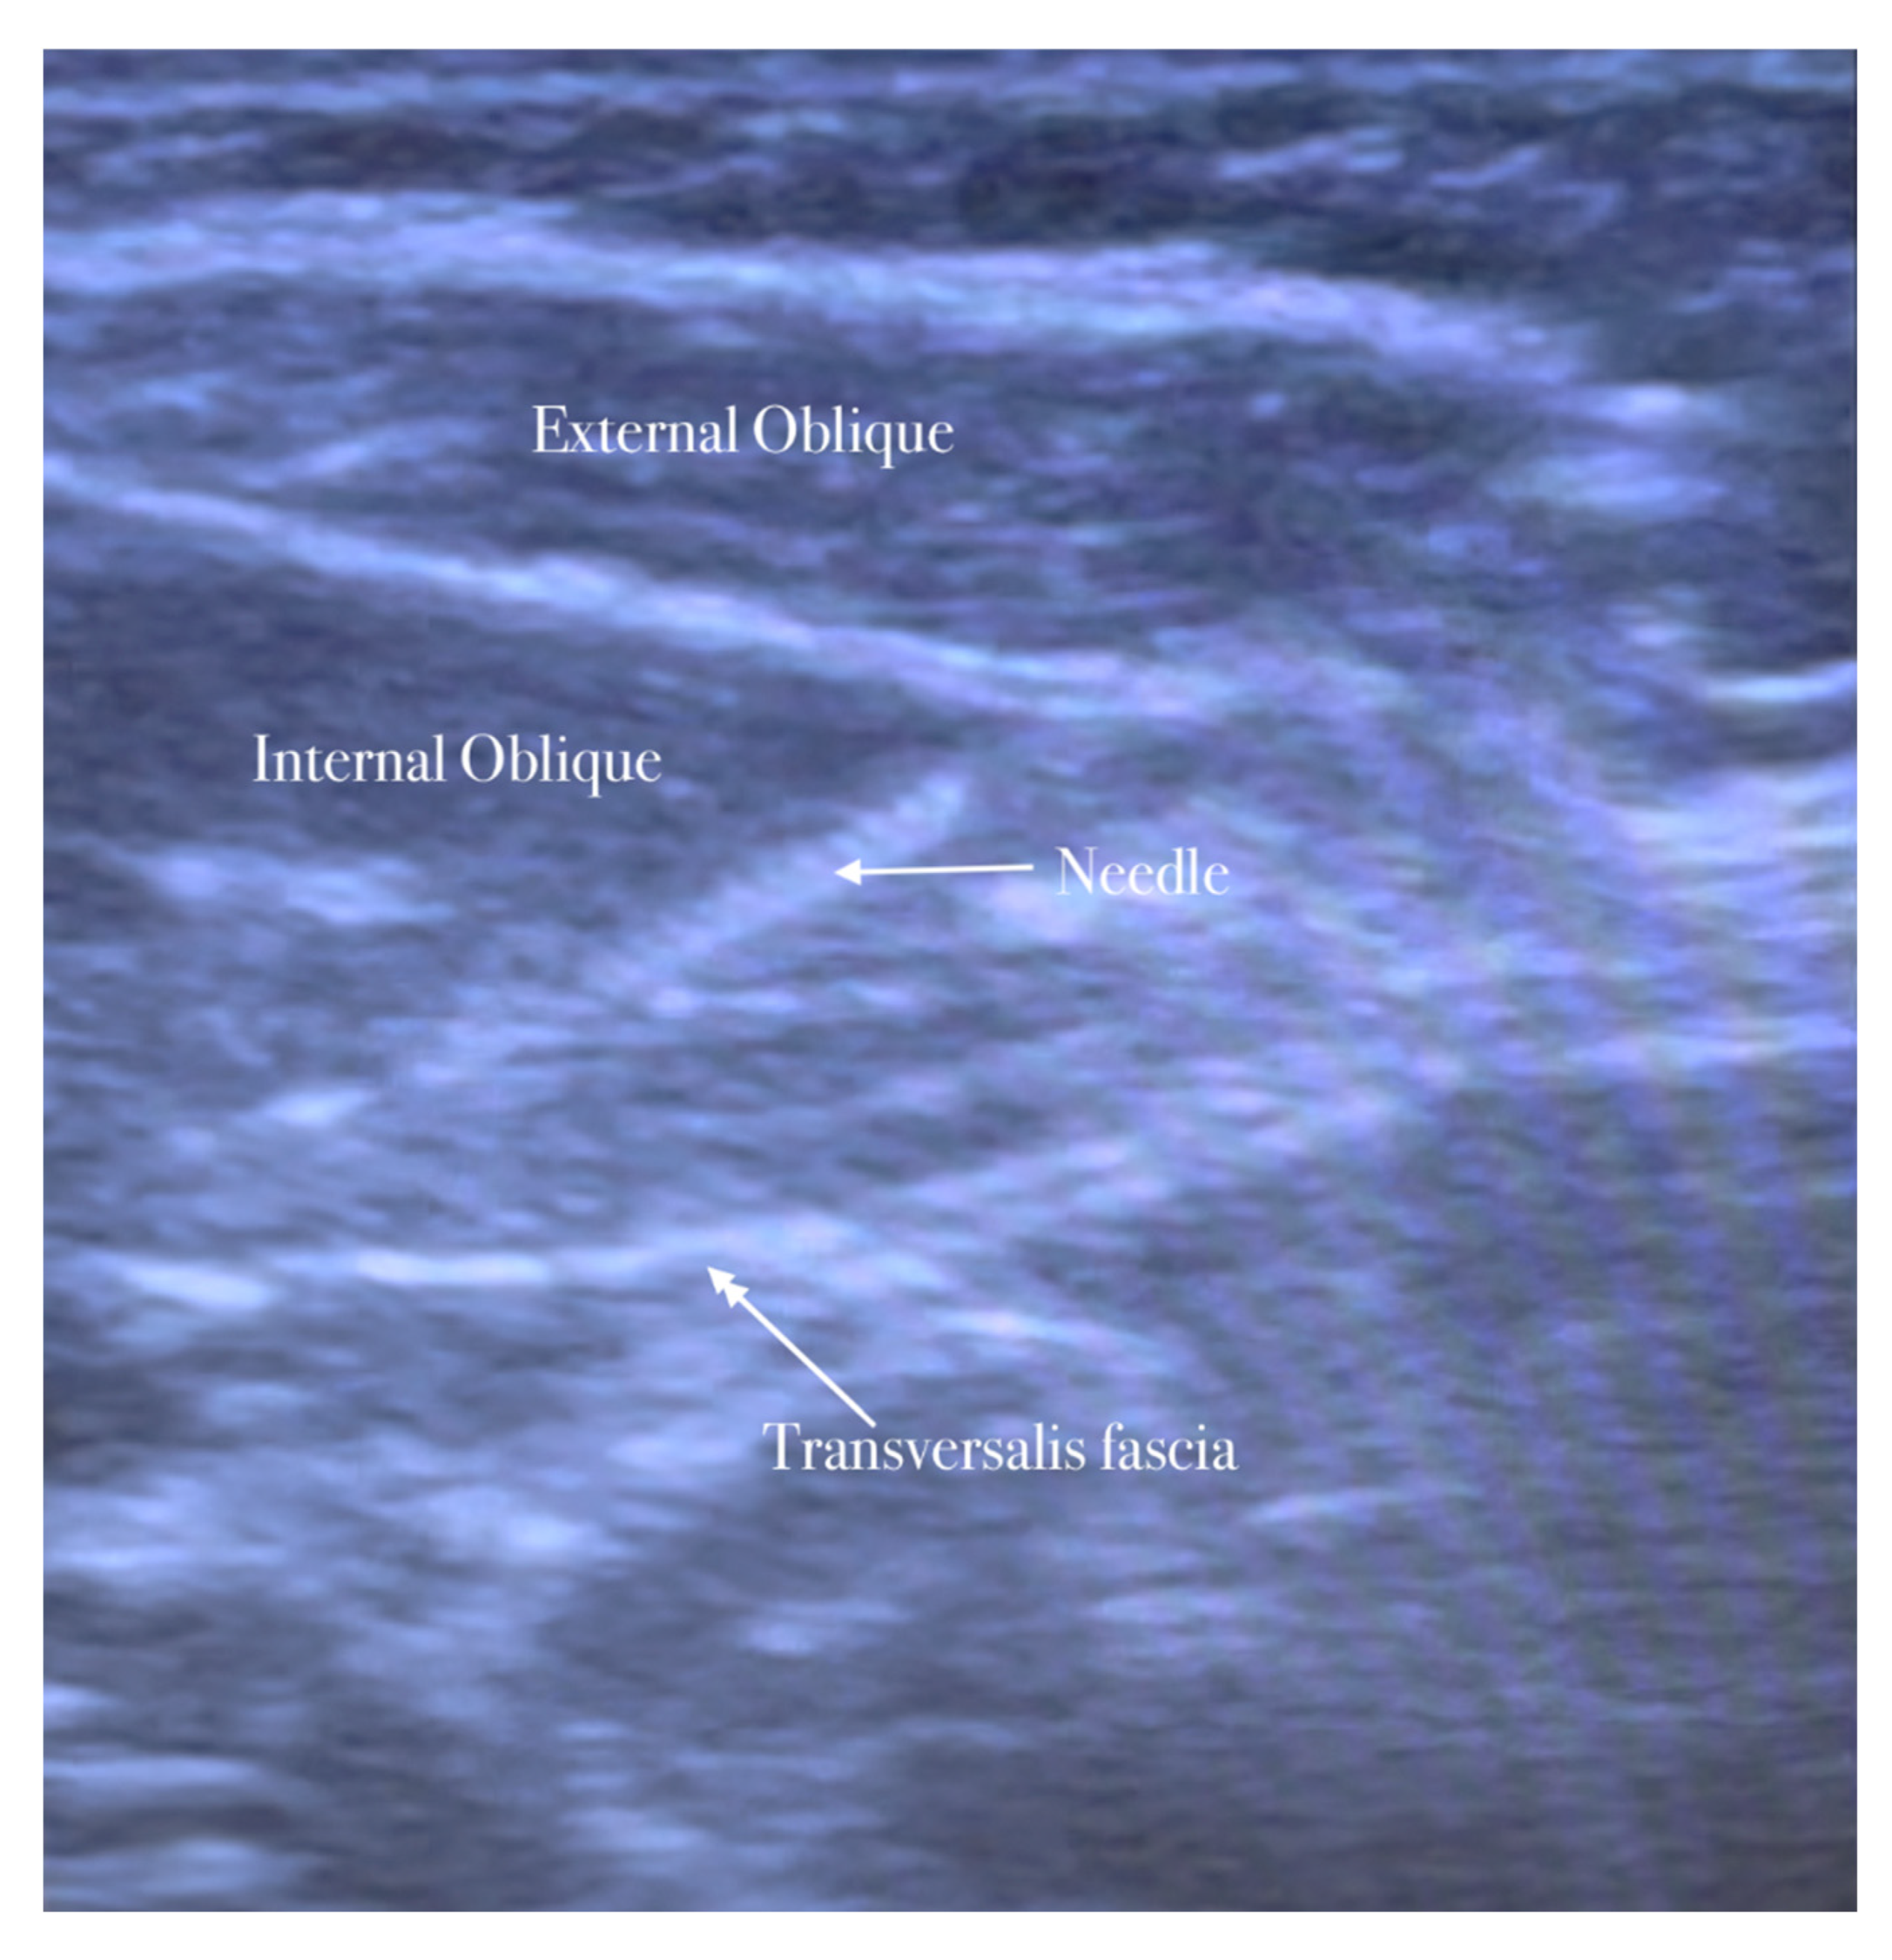

The needle is inserted in the plane in a medial-to-lateral direction; 10 mL of anesthetic (Mepivacaine 10 mg/mL–Ropivacaine 7.5 mg/mL) is injected in the transversus abdominis plane, as seen in Figure 1, Figure 2, Figure 3 and Figure 4.

The needle is inserted through the three abdominal muscles in the transversus abdominis plane.

The patient lies in a supine position. The ilioinguinal–iliohypogastric nerves block is performed unilaterally using ultrasound guidance and placed in the transversus abdominis plane. Ilio-hypogastric and ilioinguinal nerves are the terminal branches of the anterior rami of the L1 spinal nerve. They emerge from the upper part of the lateral border of the psoas major muscle; both nerves cross obliquely anterior to the quadratus lumborum and iliacus muscles and perforate the transverse abdominis muscle near the anterior part of the iliac crest. In the anterior abdominal trunk, the nerves travel between the transverse abdominis and the internal oblique muscles [15].

A high-frequency, linear, high-resolution probe is initially kept perpendicularly on the lateral abdominal wall at the midaxillary line between the anterior superior iliac spine and the navel. In this place, the three abdominal muscles are seen below the subcutaneous fat and the plane between the internal oblique, and the transversus abdominis muscle is identified. The peritoneum can be seen as the fascia layer underneath the transversus abdominis muscle. Between the layers of the transversus abdominis and the internal oblique muscle, the splitting of the fascia layer is usually observed. It is on this plane where the ilioinguinal and iliohypogastric nerves pass through. Sometimes, both nerves pierce the internal oblique and appear between the internal and external oblique muscles.